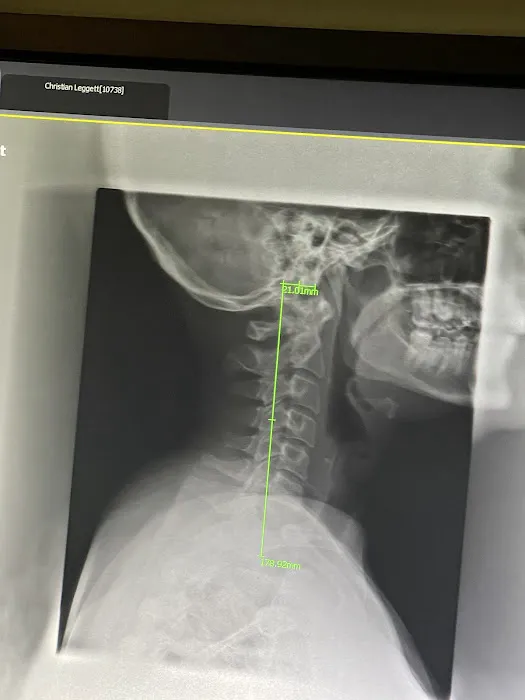

Raleigh Chiropractic and Wellness offers a comprehensive range of services designed to provide lasting relief and promote long-term health. Dr. Mike's expertise allows him to treat a wide variety of common conditions with a personalized and effective approach. The clinic is equipped with advanced technology and therapies, ensuring that patients receive the most current and effective treatments available. This commitment to innovation is a key part of their success. The practice is highly rated and known for its corrective chiropractic care, which is a significant draw for those seeking more than just temporary fixes. Dr. Mike utilizes two decompression tables, a crucial asset for patients with low back pain who want to avoid surgery. He also offers Piezowave2 therapy, a cutting-edge treatment for soft tissue issues, which demonstrates his versatility and dedication to finding the right solution for each patient. The range of conditions he treats, from low back pain and headaches to joint pain and carpal tunnel, highlights his broad expertise. His ability to address the "why" behind the pain, using x-rays and a thorough spinal exam, ensures that the treatment is targeted and effective, leading to true healing. This commitment to a detailed and results-oriented approach is what truly sets Raleigh Chiropractic and Wellness apart.

Feb 09, 2025 · Alicia GromickoThis has changed my mobility!I started with Dr. Hoehle in Sept 2023 with some limited mobility in my ease of movement and wearing braces/compression gloves. I was experiencing neuropathy type pain in my hands/feet with an overall diminished quality of life.He did X-rays to fully understand the reasons why I was experiencing said pain and every area that I complained of was addressed/taken seriously. Including my wrists and ankles!When I developed migraines presenting in my sinuses, Dr. Hoehle treated that additionally for me with my other problem areas as a whole individual. He is respectful, mindful, and genuinely listens. His pricing included the full scope of his recommended therapies and he averaged that amount out per visit and an estimated duration of time to make it the most affordable plan he could for me.My follow-up X-rays showed vast improvements in the problematic areas and now I am down to one visit weekly with a much improved quality of daily life, I have encouraged my adult children to seek treatment here with him as well. My eldest has seen initial results already.This was the first winter in almost 7 years I did not need to wear adaptive devices to endure the pain and be able to live my life. It was a freedom I didn’t expect to regain. I’d give him 10 stars if it would allow.Update: 2/15/25Started using the PWave. It used sound waves to break up scar tissue in affected and painful areas. It lasts 5-10min and feels like an intense deep tissue massage (I also have a high pain tolerance).I felt some results immediately and 2 days after I feel like a different person!I Spring cleaned! Definitely ask about this treatment because it has put quality back in my day to day physical health.